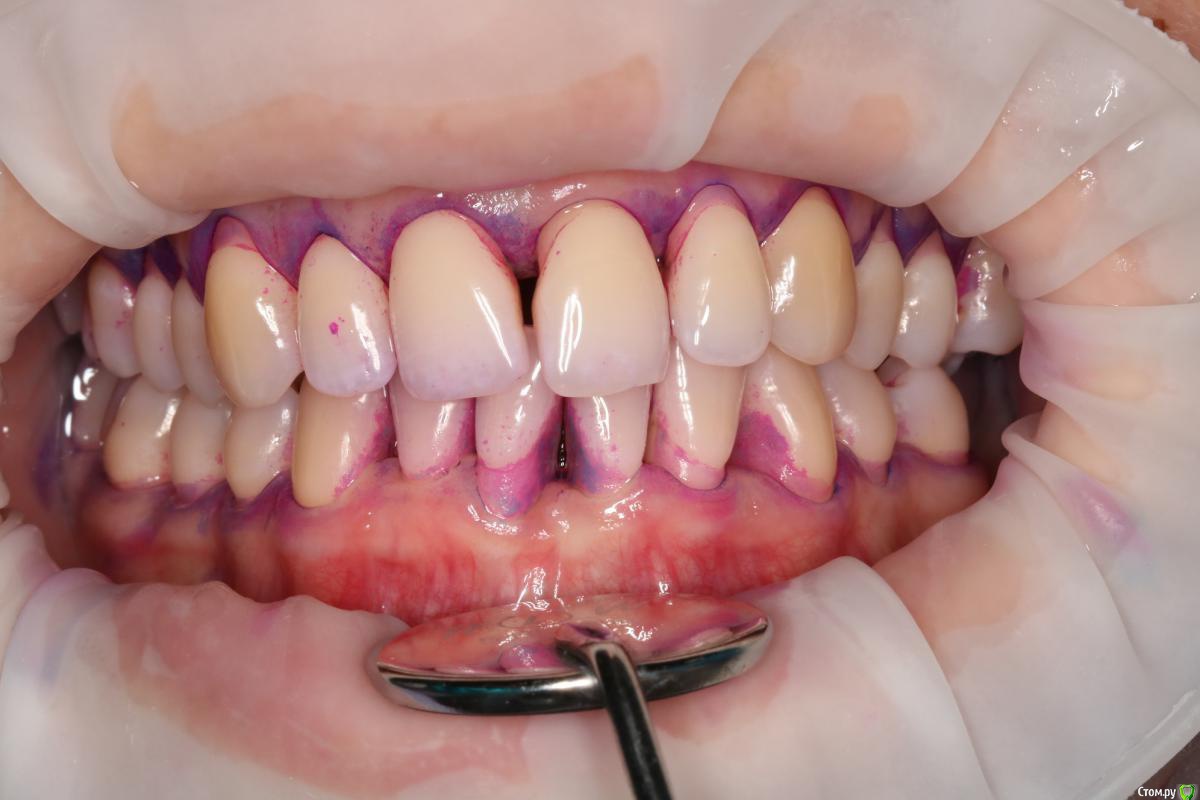

NataliaNN Опубликовано 8 ноября, 2018 Поделиться Опубликовано 8 ноября, 2018 Добрый день! У меня довольно сложная с деснами, генерализованный пародонтит, который обострился после родов и ГВ. Десны были очень воспалены, стали разворачиваться зубы. Я прошла курс чисток для лечения десен, уроки гигиены. Благодаря чему острый период воспаления прошел, сейчас состояние пародонта стабилизируется. Для дальнейшего лечения хирург планирует восстановление костной ткани на 21 и 46 зубах, и закрытие рецессий на 41, 24,25,26. А через полгода после операций можно заняться ортодонтией. Ортодонт придерживается другого мнения, сразу брекеты, а потом хирургические операции, аргументируя тем, что во время ношения брекетов результат операций может быть сведен к нулю. Хирург и ортодонт из разных клиник. Оба врача хорошие специалисты и все свои доводы аргументируют, но их точки зрения диаметрально противоположны. С чего же все-таки начать, подскажите, пожалуйста. Очень не хочется усугубить и так непростую ситуацию, к тому же все это очень затратно. Очень важно услышать мнение других специалистов. (Зубы 37,36 были потеряны в подростковом возрасте). Ссылка на комментарий

колесников Опубликовано 9 ноября, 2018 Поделиться Опубликовано 9 ноября, 2018 Не вижу смысла в ортодонтическом лечении в вашем случае (если только с 21), также сомнения в костной пластике 21,46 и в закрытии рецессии на данном этапе. Рекомендовал бы сейчас поставить импланты 36,37 с десневой пластикой , с ортопедом провести диагностику окклюзии,выявить суперконтакты,вам регулярно использовать ирригатор и через 3 мес оценить усадку десны (фронт низ-верх )и запланировать пластику рецессий. Проблема с 21 решается ортопедическим или ортодонтическим путём Ссылка на комментарий